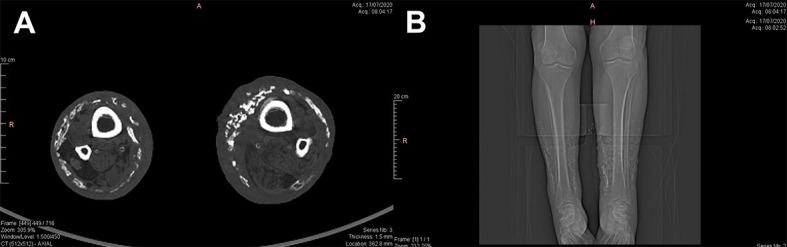

Lower limb ulcers secondary to chronic venous disease (CVD) are a significant public health problem in Brazil and account for about 70% of these ulcers. Despite recent technological advances and the various therapeutic options for treatment of these chronic injuries, several factors may be involved in resistance to treatment. Dystrophic calcinosis cutis (DCC) is a rare and often underdiagnosed condition that, when in conjunction with CVD, may be associated with a refractory healing process. In this article, we report a case of DCC in a patient with CVD and discuss its etiology, pathophysiology and possible treatment options.

慢性静脉疾病(CVD)继发的下肢溃疡在巴西是一个重大的公共卫生问题,约占此类溃疡的70%。尽管近年来技术有所进步,且针对这些慢性损伤有多种治疗选择,但治疗抵抗可能涉及多个因素。营养不良性皮肤钙化症(DCC)是一种罕见且常被漏诊的疾病,与CVD并存时,可能与难治性愈合过程相关。在本文中,我们报告了1例患有CVD的DCC患者,并讨论其病因、病理生理学及可能的治疗选择。